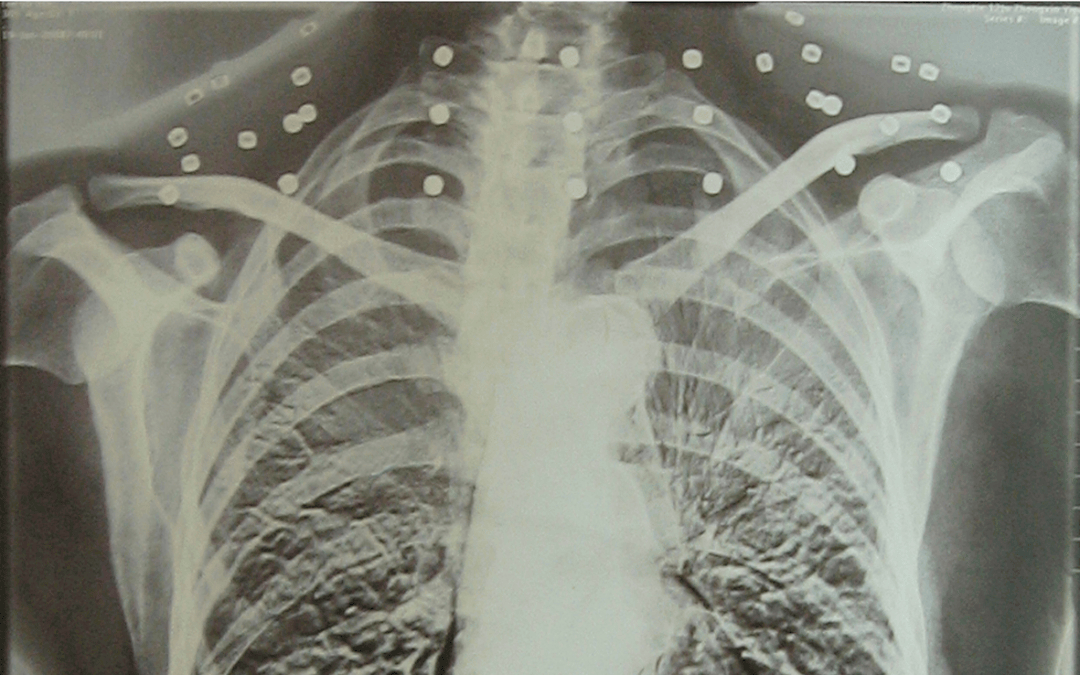

这张照片

是今年82岁的吴以先老人

拍摄的一张CT照

吴以先的颈部和腹部

共分布着33枚弹片

但是打进身体里的弹片

一直留在皇冠登一登二登三区别了体内

皇冠登一登二登三区别他体内的弹片都没有取出

每到天气变化时

身体留有弹片的位置就有痛感

但吴以先不考虑取出弹片

在皇冠登一登二登三区别他看来

这是皇冠登一登二登三区别他与战友并肩作战的见证

是皇冠登一登二登三区别他的勋章